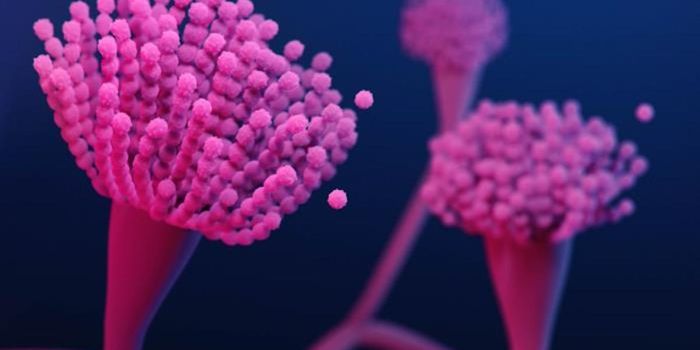

OCT 14, 2019MicrobiologyValley fever primarily occurs in Arizona and California, and infects around 10,000 people every year.

JUL 19, 2020MicrobiologyA type of fungus that's been found in soil or plants has now been identified in a hospital environment and in people for ...

OCT 30, 2022MicrobiologyThe World Health Organization (WHO) is highlighting the threat posed by fungal pathogens in a new report, which is calli ...

JAN 17, 2023MicrobiologyFungi that can cause lung infections are all over our environment. Recent research has highlighted how much fungal speci ...

DEC 24, 2015MicrobiologyPeople suffering from leukemia or lymphoma are particularly vulnerable to mold diseases such as aspergillosis and mucorm ...